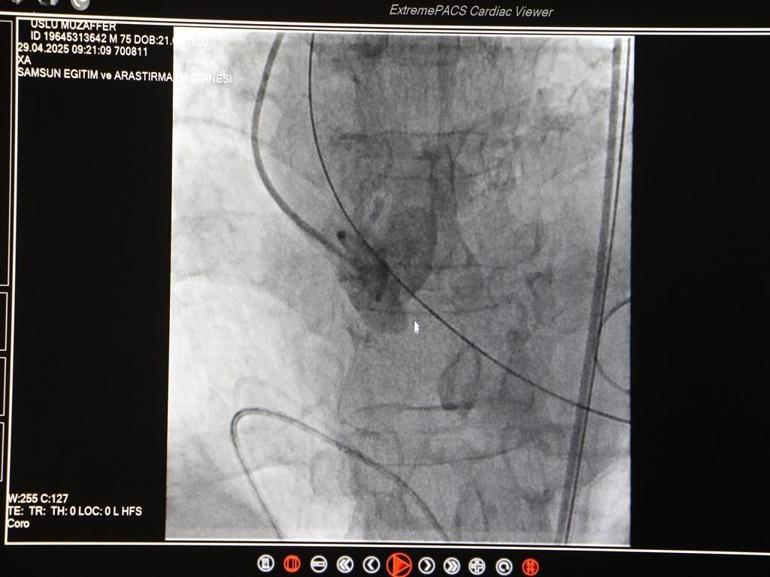

Amasya'nın Merzifon ilçesinde yaşayan Muzaffer Uslu, nefes darlığı ve bayılma şikayeti ile 21 Nisan'da Merzifon Devlet Hastanesi'ne başvurdu. Uslu, aort kapağının ileri düzeyde daralması nedeniyle 23 Nisan'da Samsun Eğitim ve Araştırma Hastanesi’ne sevk edildi. Burada Samsun Üniversitesi Tıp Fakültesi Kardiyoloji ve Anabilim Dalı Öğretim Üyesi Doç. Dr. Mustafa Yenerçağ ile alanında uzman doktorlar, TAVI (Transcatheter Aortic Valve Implantation) yöntemi ile ameliyat yapılmasına karar verdi. Hasta Muzaffer Uslu, 29 Nisan'da ameliyata alındı. 50 dakika süren ameliyatın ardından hasta Uslu, 1 gün yoğun bakım kaldı ve servise alındı.

Doç. Dr. Yenerçağ, "Bu konuda iyice hazırlandık. Bu konuda deneyimli hocalarımızdan da bilgi aldık. Sonrasında hastamıza Doç. Dr. Serkan Sivri, ben, asistanlarımdan Dr. Berkant Öztürk ve Dr. Enes Kaya ile beraber ayrıca anesteziden de Uzm. Dr. Aynur Kaynar hocamızla beraber ortak bir ekiple TAVI işlemini yapmaya karar verdik ve 2 gün önce hastamıza başarılı bir şekilde sağ kasığından girerek genel anestezi vermeden başarılı bir şekilde kalp kapağını değiştirdik. TAVI yöntemiyle kalp kapağını değiştirdik. İşlemimiz gayet başarılı geçti. 1 gün yoğun bakımda hastamızı takip ettik. 1 gündür de servise takip ediyoruz. Bir aksilik olmadığı sürece de yarın taburcu etmeyi planlıyoruz" diye konuştu.